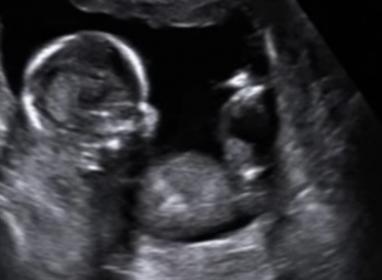

I'm supposed to be team green but since day 1 everyone has said they think it's a boy. I'm 27 weeks now and feeling anxious to find out! Here are some pics from the 16 week scan video. The pics I have from the 20 week scan don't show anything at all. Do you think thats a penis or could it be the cord or something?

Attachment 31149

Maybe boy, but 3D is not good for gender. Any more 2D pics?